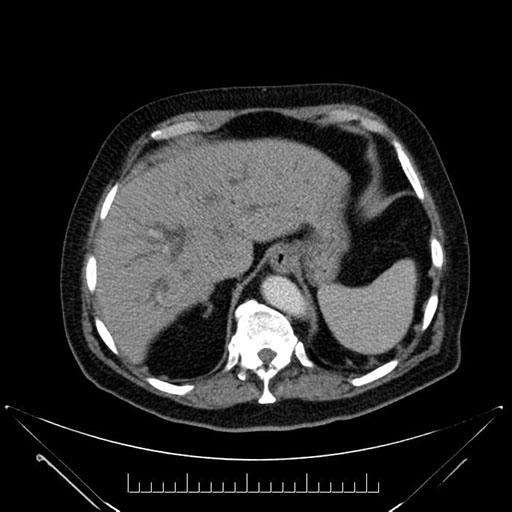

Whipple (pancreaticoduodenectomy) [case 7]

Imaging Analysis

Look through the patient's CT scan to identify any areas of concern for the necessary procedure.

Axial - stented